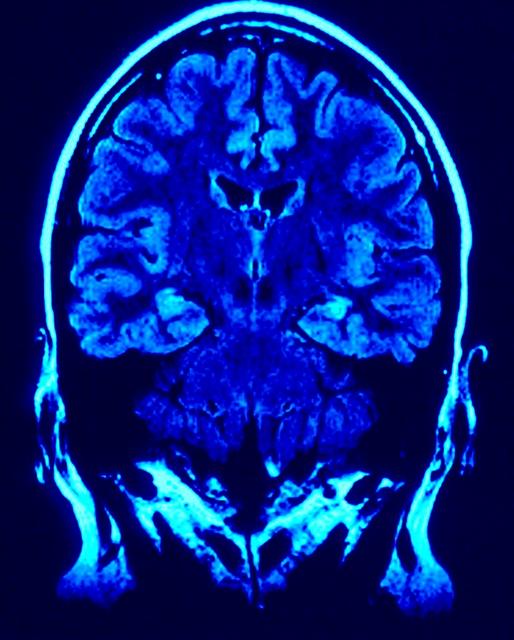

Creutzfeldt-Jakob

Determinate cellule del sistema immunitario potrebbero aiutare a spiegare perché le persone giovani sono più a rischio, rispetto a quelle più anziane, di sviluppare la variante della malattia di Creutzfeldt-Jakob (vCJD). Le scoperte, pubblicate nella rivista Journal of Immunology, potrebbero eventualmente condurre a nuovi test per la malattia e a trattamenti per impedire ai prioni responsabili della malattia di diffondersi al cervello e al sistema nervoso centrale (CNS).